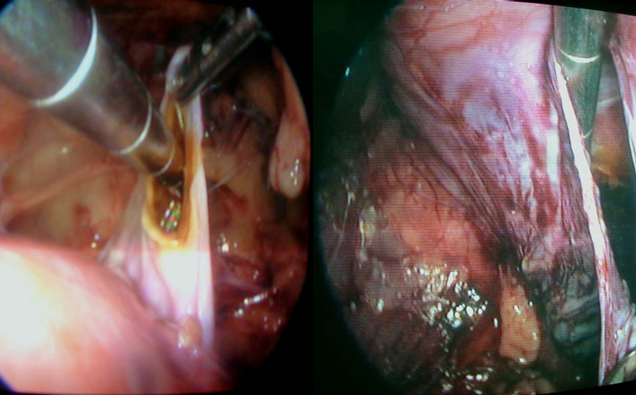

4、腹腔镜泌尿外科手术

应用腹腔镜技术进行各种泌尿外科疾病的手术治疗已是当今泌尿的主要手术方式。目前,几乎所有需开放手术治疗的泌尿外科疾病都可采用腹腔镜手术进行治疗。我科开展了腹腔镜内静脉结扎术以及肾囊肿去顶术,精索静脉曲张高位结扎术,肾上腺肿瘤切除术及泌尿系肿瘤等,均获得满意疗效。该手术的特点是需做3-4个1cm左右的小切口即可进行手术。它具有手术创伤小、出血少、术后恢复快、对体力影响小等优点。